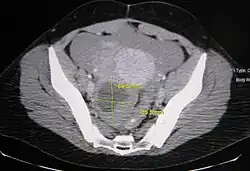

An Axial CT demonstrating a large hemorrhagic ovarian cyst. The cyst is delineated by the yellow bars with blood seen anteriorly.

Ovarian cysts are usually diagnosed by pelvic ultrasound, CT scan, or MRI, and correlated with clinical presentation and endocrinologic tests as appropriate.[15] Ultrasound is the most important imaging modality, as abnormalities seen in a CT scan sometimes prove to be normal in ultrasound.[5][8] If a different modality is needed, then MRIs are more reliable than CT scans.[5]

Follow-up imaging in women of reproductive age for incidentally discovered simple cysts on ultrasound is not needed until 5 cm, as these are usually normal ovarian follicles. Simple cysts 5 to 7 cm in premenopausal females should be followed yearly. Simple cysts larger than 7 cm require further imaging with MRI or surgical assessment. Because they are large, they cannot be reliably assessed by ultrasound alone; it can be difficult to see posterior wall soft tissue nodularity or thickened septation due to limited ultrasound beam penetrance at this size and depth. For the corpus luteum, a dominant ovulating follicle that typically appears as a cyst with circumferentially thickened walls and crenulated inner margins, follow up is not needed if the cyst is less than 3 cm in diameter.[8] In postmenopausal women, any simple cyst greater than 1 cm but less than 7 cm needs yearly follow-up, while those greater than 7 cm need MRI or surgical evaluation, similar to reproductive age females.[16]